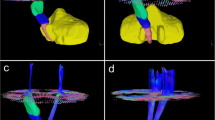

DWI data were corrected for eddy currents prior to DTI fitting using FSL [13]. ROIs for the CST and the PS-CST were obtained using the John Hopkins University [JHU] DTI-based white matter atlas (https://identifiers.org/neurovault.image:1401) (Fig. 1) non-rigidly transformed to each subject’s DWI image space. Similarly, to obtain the ICH and PHE ROIs in each subject’s DWI space, non-rigid transformations were computed between SWI and DWI, and between FLAIR and DWI image spaces. All image transformations were done using the NiftyReg software package [14]. Finally, mean FA and MD were computed in the CST and in the PS-CST using the obtained ROIs. To obtain the ICH probability map, we summed all the lesion masks and divided by the number of patients to give a lesion probability at each voxel.

We included 42 adult patients with spontaneous supratentorial deep ICH (flow chart in Fig. 2). Group probability maps showed the ICH lesion distribution reported in Fig. 3. Table 1 summarizes clinical and radiological characteristics in the entire cohort, including PS-CST mean rFA and rMD. Median age was 62 years (IQR 52–72), and median ICH volume was 5.4 mL (IQR 3.0–11.7). Thirteen patients (31.0%) had poor functional outcome (mRS > 2) at 6 months. Mean rFA was 1.024 (SD 0.139), and mean rMD was 1.046 (SD 0.312). Table 2 describes univariable logistic regression models for the association between clinical and radiological variables, including rFA and rMD, and poor long-term functional outcome.

Only one study has compared the predictive performance of DTI parameters and the ICH score [21] and found that the prognostic value of the ICH score substantially surpassed that of CST-related DTI metrics (AUC 0.74 vs. 0.44; p = 0.01 for mRS > 2); moreover, the combination of the DTI metrics with the ICH score did not improve the prognostication of outcome. Our findings appear more promising regarding the potential predictive clinical value of DTI metrics; our estimates suggest that combined models with DTI and non-DTI variables (including ICH score) might provide better outcome discrimination than ICH score alone, although the difference in discrimination was not statistically significant. The discrepancy might be due to differences in population characteristics: 68.8% of patients included in the cited study had lobar ICH, and given their variable location and impact on CST fibres, lobar ICH is likely to have less consistent impact on CST. By contrast, we included only patients with deep supratentorial ICH; as shown in Fig. 3, the ICH location in our cohort included putamen, globus pallidus, internal capsule, thalamus and external capsule. Haemorrhage and peri-haematomal oedema in these regions are expected to consistently affect the CST via both direct disruption or displacement of fibre tracts and indirect mechanisms including oedema, inflammation and early Wallerian degeneration. Our study suggests that in acute ICH, DTI metrics in the pons can detect microstructural alterations of the CST which are associated with 6-month mRS.